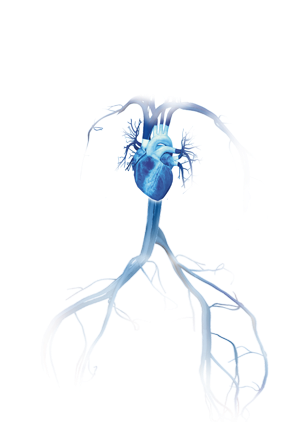

Coração

CORAÇÃO